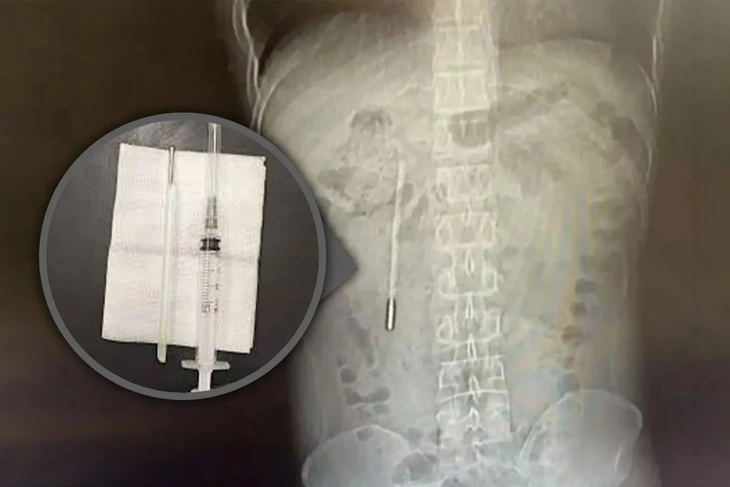

Kết quả chụp X-quang phát hiện một dị vật trong tá tràng, được các bác sĩ xác định là chiếc nhiệt kế thủy ngân. Do đầu nhọn của nhiệt kế cắm trực tiếp vào thành ruột, bệnh nhân đối mặt nguy cơ cao bị thủng ruột và xuất huyết nội nghiêm trọng.

Các bác sĩ phẫu thuật lấy dị vật ra ngoài chỉ trong 20 phút. Đây là ca can thiệp đòi hỏi độ chính xác cao do nhiệt kế lưu lại trong cơ thể quá lâu và nằm gần ống mật, tiềm ẩn nguy cơ tổn thương thành ruột trong quá trình thao tác.

Chiếc nhiệt kế sau khi được lấy ra vẫn còn nguyên vẹn, song các vạch đo nhiệt độ đã phai mờ theo thời gian.